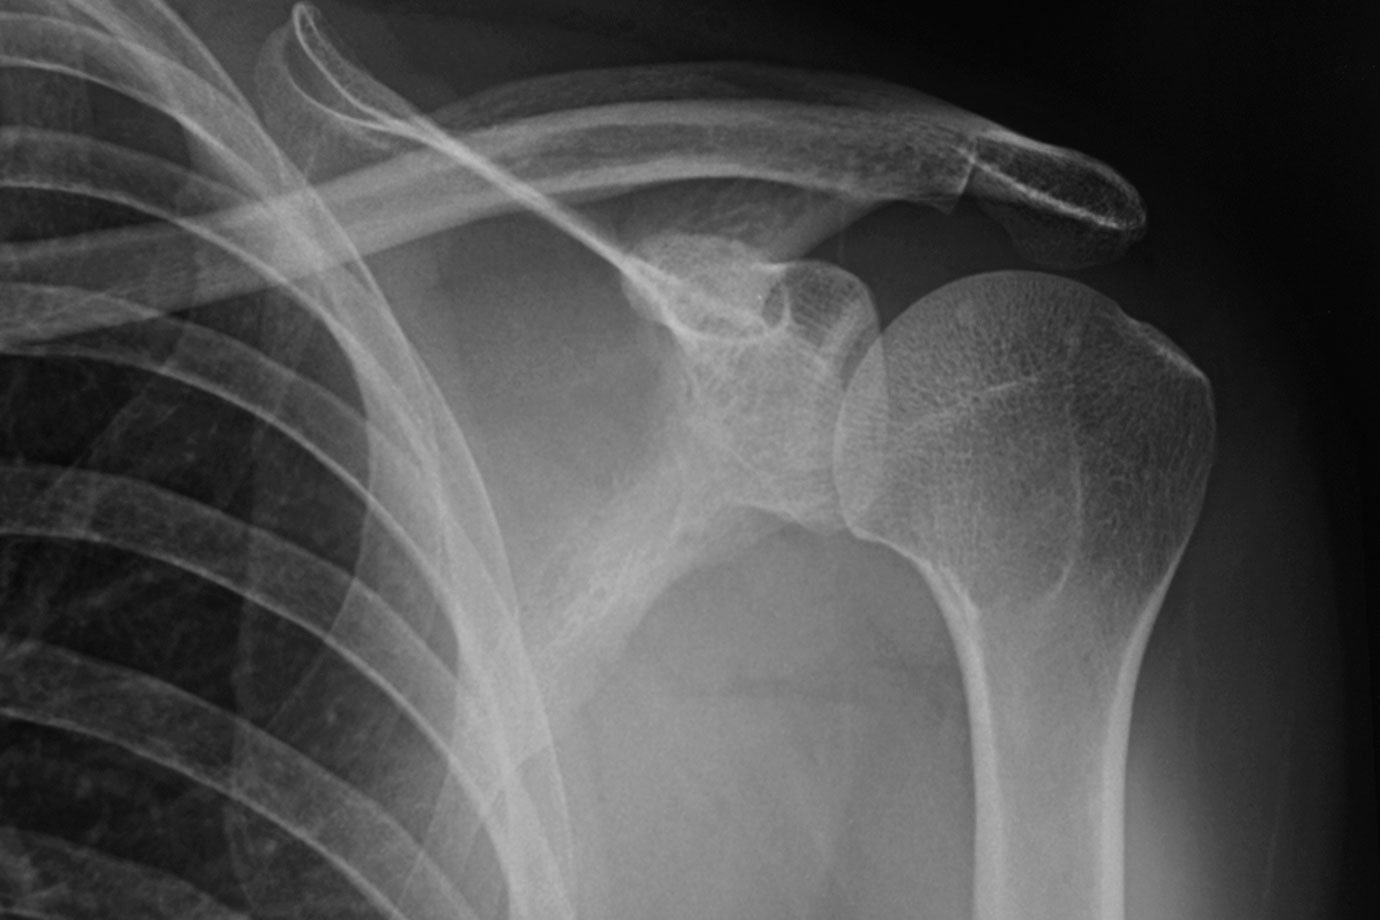

Ossos: novo material não tem grau de toxicidade com novo biomaterial (Miguel Sotomayor/Getty Images)